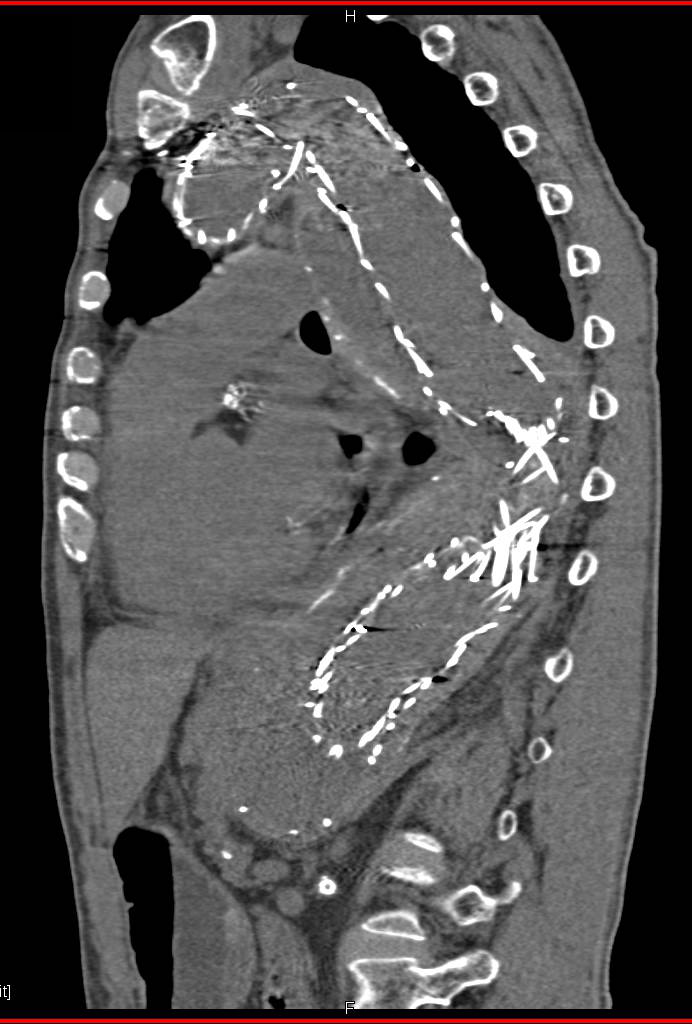

CTA Runoff with Vascular Grafts and Peripheral Vascular Disease (PVD)